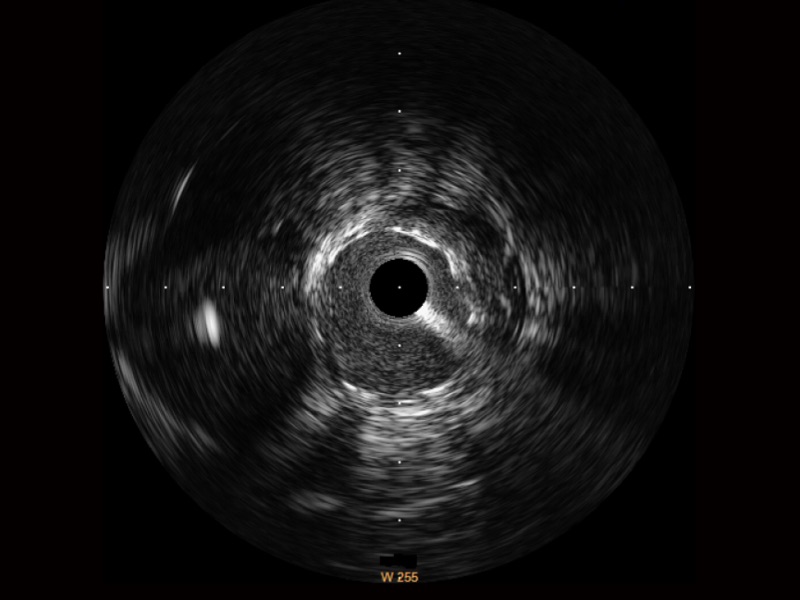

传统IVUS图像

对比传统IVUS导管成像,狗万官方网站宽频IVUS图像的近场支架梁显影更细腻,远场中膜外血管仍清晰可辨,兼顾远中近,兼顾分辨力与穿透深度